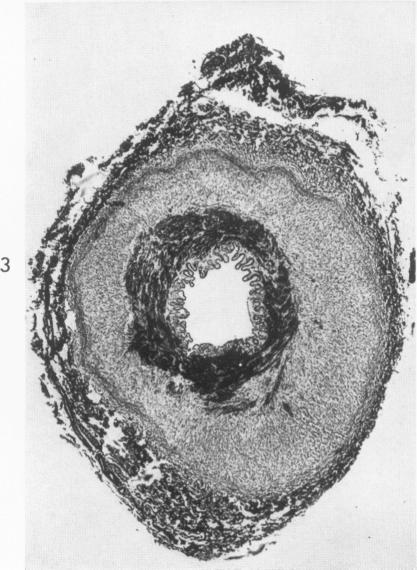

FIBROMUSCULAR HYPERPLASIA OF RENAL ARTERIES IN HYPERTENSION.

Am J Pathol. 1963 Dec;43(6):955-67.